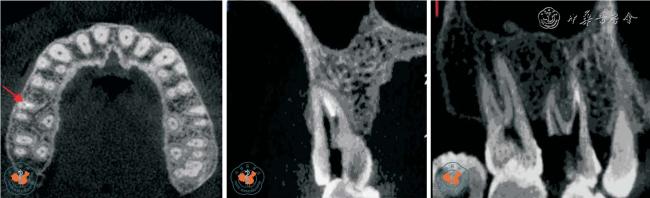

5. 诊断根管侧壁穿孔:Young16报道,对普通根尖片不能诊断根管侧壁穿孔的病例用CBCT 进行分析,发现CBCT 图像显示根管侧壁穿孔明显,有助于早诊断、早治疗,提高治疗效果。 Lofthag-Hansen 等17也指出,CBCT 较根尖片对根管侧壁穿孔的诊断率较高。 另外,传统牙片显示根管充填良好,未见侧壁穿孔,牙胶尖定位显示窦道来源于牙根侧方,通过CBCT 影像分析,发现根管侧壁穿孔位置,行穿孔修补术后,疗效良好(图7)。

图7 CBCT 轴位、MPR 及VR 重建上颌中切牙清晰显示根管侧壁穿孔

6. 牙髓病治疗失败原因的评价:根管充填不严密、超充、遗漏根管、器械断入是牙体牙髓疾病治疗失败的主要原因。 而普通口内X 线摄片常因采用不同角度投照,胶片、牙齿、X 线球管三点不能垂直在一条直线上,往往使图像相互重叠,不能清晰显示牙根走向、细小根管弯曲程度,对临床医生有误导作用,致使根管治疗后仍有反复肿胀等症状。 通过对根管治疗后仍有症状的牙体牙髓病患者行CBCT 检查,运用三维成像技术对患牙进行多层面分析,均明确病因,提高了根管治疗的成功率18,见图8 ~9。

图8 CBCT 轴位、CPR 及MIP 重建显示左侧中切牙后方舌侧骨板因左上尖牙超充引起继发感染

图9 CBCT 轴位及MIP 重建显示右上颌6 近中根管有高密度异物(断针位于右上颌6 近中根管内)